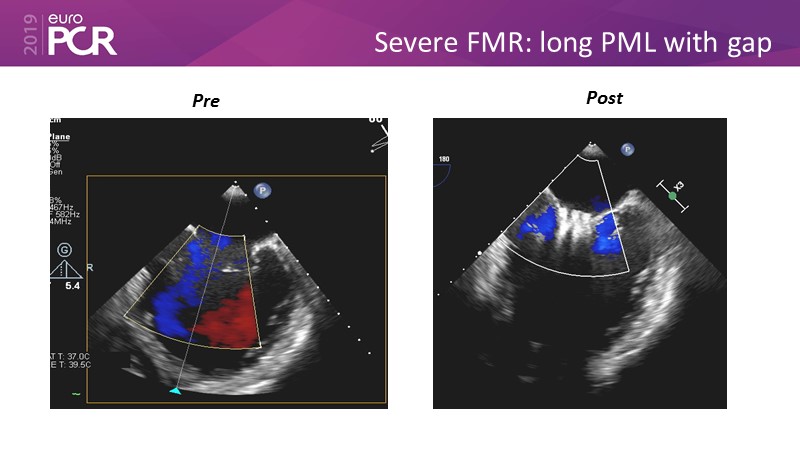

- To learn how will product innovation (Mitraclip NTR / XTR) drive improvement in procedural and clinical outcomes (EXPAND)